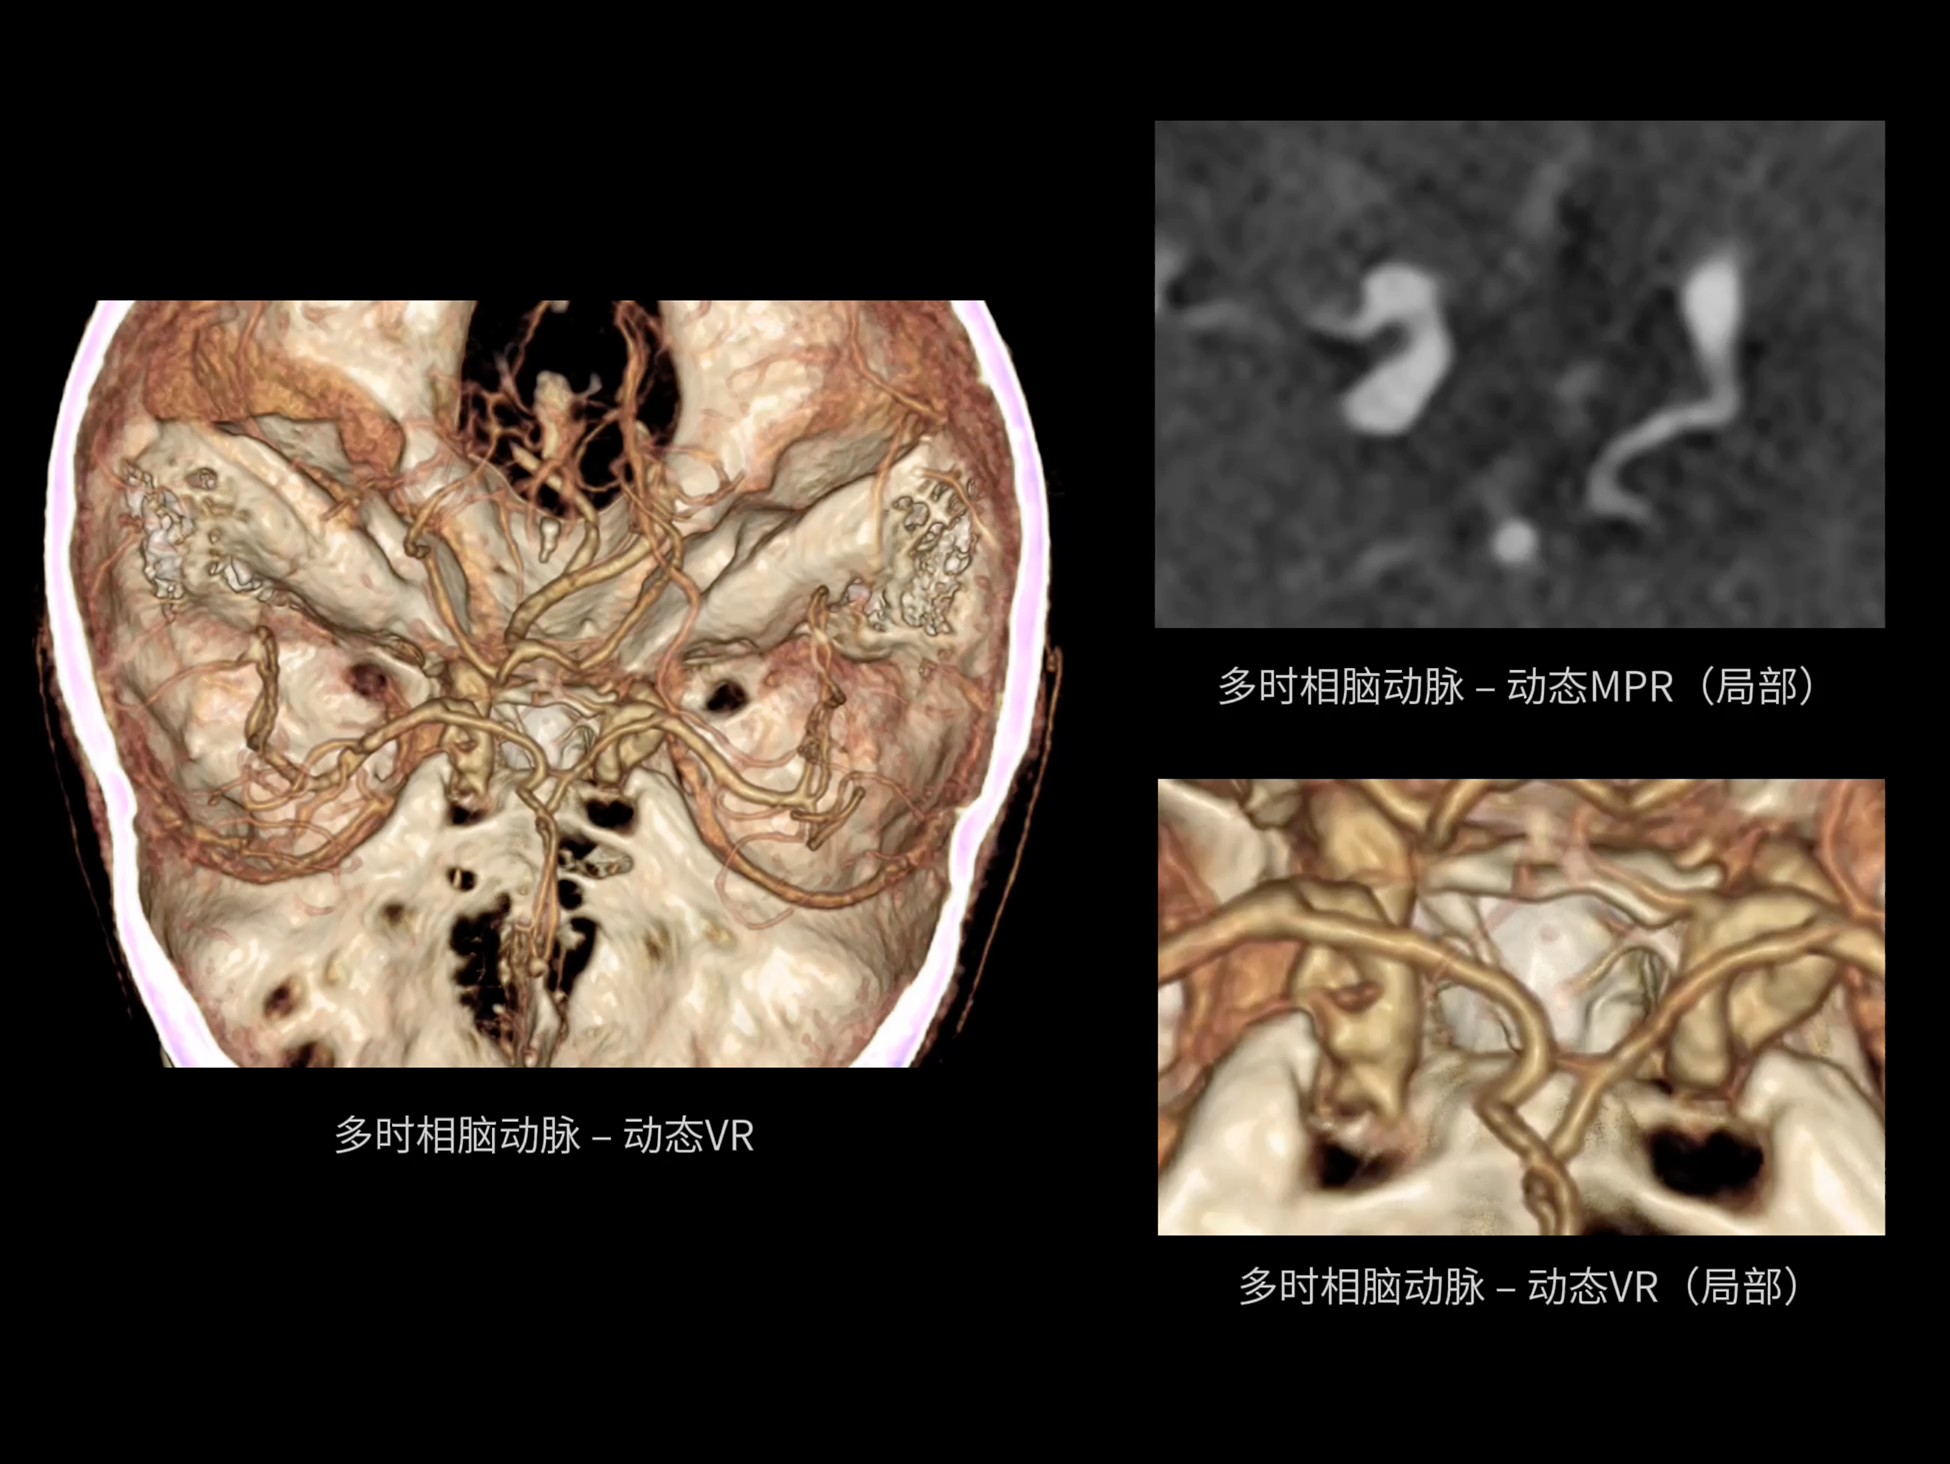

全身运动

uCT SiriuX® 以全新双宽体系统架构,同步实现超高时间分辨率与宽体容积覆盖兼得,全面释放性能潜能,敏锐捕捉人体生理运动全景,带来动态影像新视角。

uCT SiriuX® 以16cm超宽Z轴覆盖,使超高时间分辨率应用于完整器官成像。无论是心脏搏动还是关节运动,整个目标区域可在同一瞬时被完整、清晰地捕捉,彻底消除时序误差,实现从“局部瞬间”到“全器官瞬时”的成像跨越。

瞬息捕捉

全器官同步

全身各部位动态CT成像